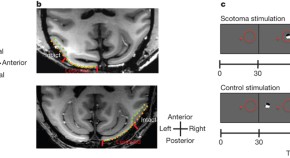

The primary visual cortex (V1) is crucial for vision, yet people with V1 injuries might still point to or avoid visual stimuli, despite having no conscious perception of them. It has been thought that this 'blindsight' relies on visual pathways that bypass the usual route from lateral geniculate nucleus (LGN) to V1. But it is shown here — using a combination of permanent and reversible lesions, behavioural testing and functional magnetic resonance imaging (fMRI) mapping — that a critical link in the alternative pathway is in fact the LGN.